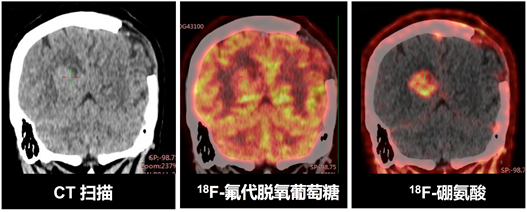

此前,为解决氨基酸类核药物标记困难、肿瘤靶向性不足的难题,刘志博及合作者基于羧基(-COO-)与三氟化硼(-BF3-)的相似性发展了一类新型含硼氨基酸核药物——18F-硼胺酸。经细胞及动物实验证实,18F-硼胺酸经特定氨基酸转运载体进入细胞,在肿瘤内有很高的特异性摄取。在该工作中,刘志博课题组通过与北京协和医院及北大肿瘤医院的合作,成功推动了18F-硼氨酸的临床研究。如下图所示,18F-硼氨酸在恶性胶质瘤摄取高(SUV=2.8-3.2),在健康脑组织摄取低(SUV=0.1-0.2),相比常规PET分子探针18F-葡萄糖,18F-硼氨酸在脑部肿瘤的诊断上有优势。该杂志同期配发了题为“First-in-human study of an 18F-labeled boramino acid: a new class of PET tracers”的专题评述,认为该工作为核医学提供了一类新型PET影像探针,有望克服传统F-18标记氨基酸探针和葡萄糖探针(18F-FDG)的缺点。评述还指出,18F-硼氨酸的提出为氨基酸类放射性药物的发展提供了新思路,其在癌症诊断以及诊疗一体硼中子俘获治疗上的临床应用值得期待。

图1. 18F-硼氨酸用于脑部肿瘤的临床诊断